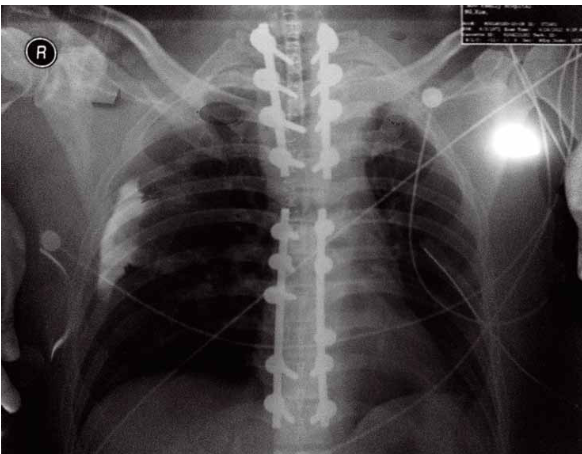

吉姆这次住院是因为赛车突发机械故障,无法减速,径直撞向护栏造成脊柱骨折。手术后,吉姆脊柱的第一到第四节被打上了四对固定的钢钉。但通过X光片可以发现,这不是他脊柱上唯一的金属部件,他脊柱腰部本来就已经存在五对钢钉,那是两年前的另外一次赛道事故造成的。当时医生就预测他会有下半身瘫痪的可能性,幸运的他神奇地恢复了肢体机能,回到了赛道上。